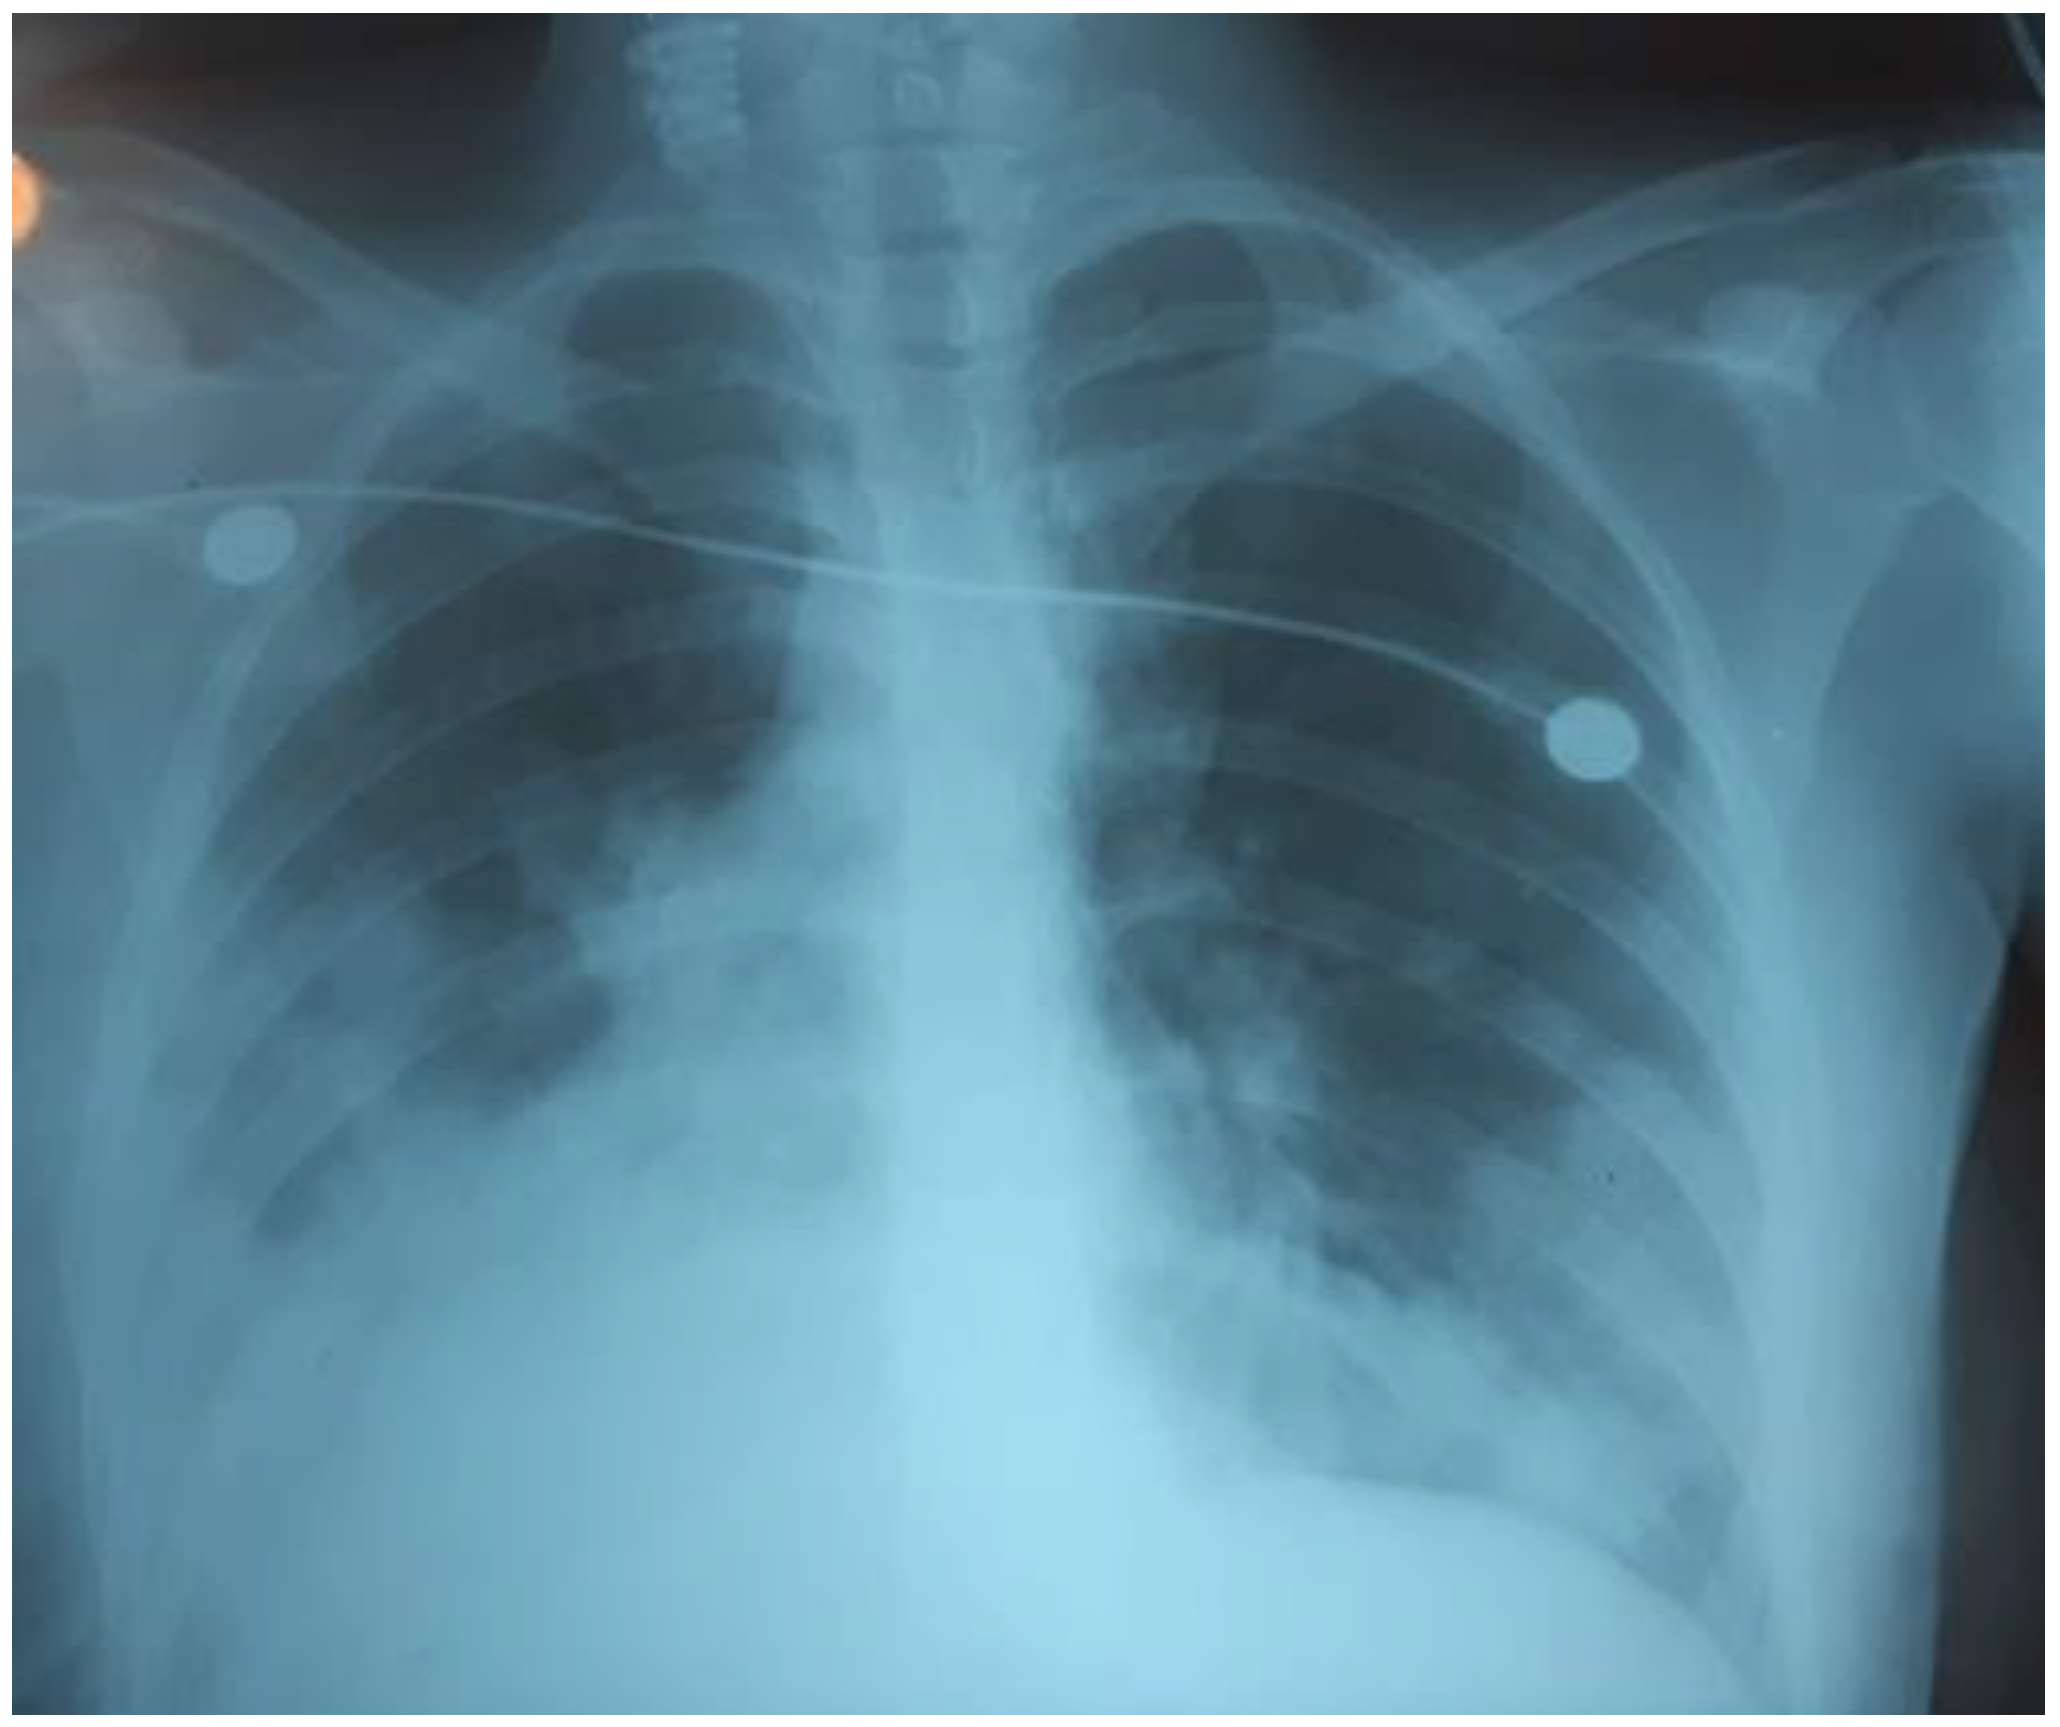

The child’s condition deteriorated within three days. The RF progressed; RR 35/min, SpO286%, oxygen dependence, HR 110/min, BP 100/60 mmHg, the symptom of capillary refill > 3 s, cold extremities. Bilateral polysegmental pneumonia was detected on the chest radiograph (Figure 3). The lung ultrasound showed signs of interstitial syndrome on both sides, alveolar consolidation on the left, left-sided hydrothorax.

Figure 3.

Bilateral polysegmental pneumonia.